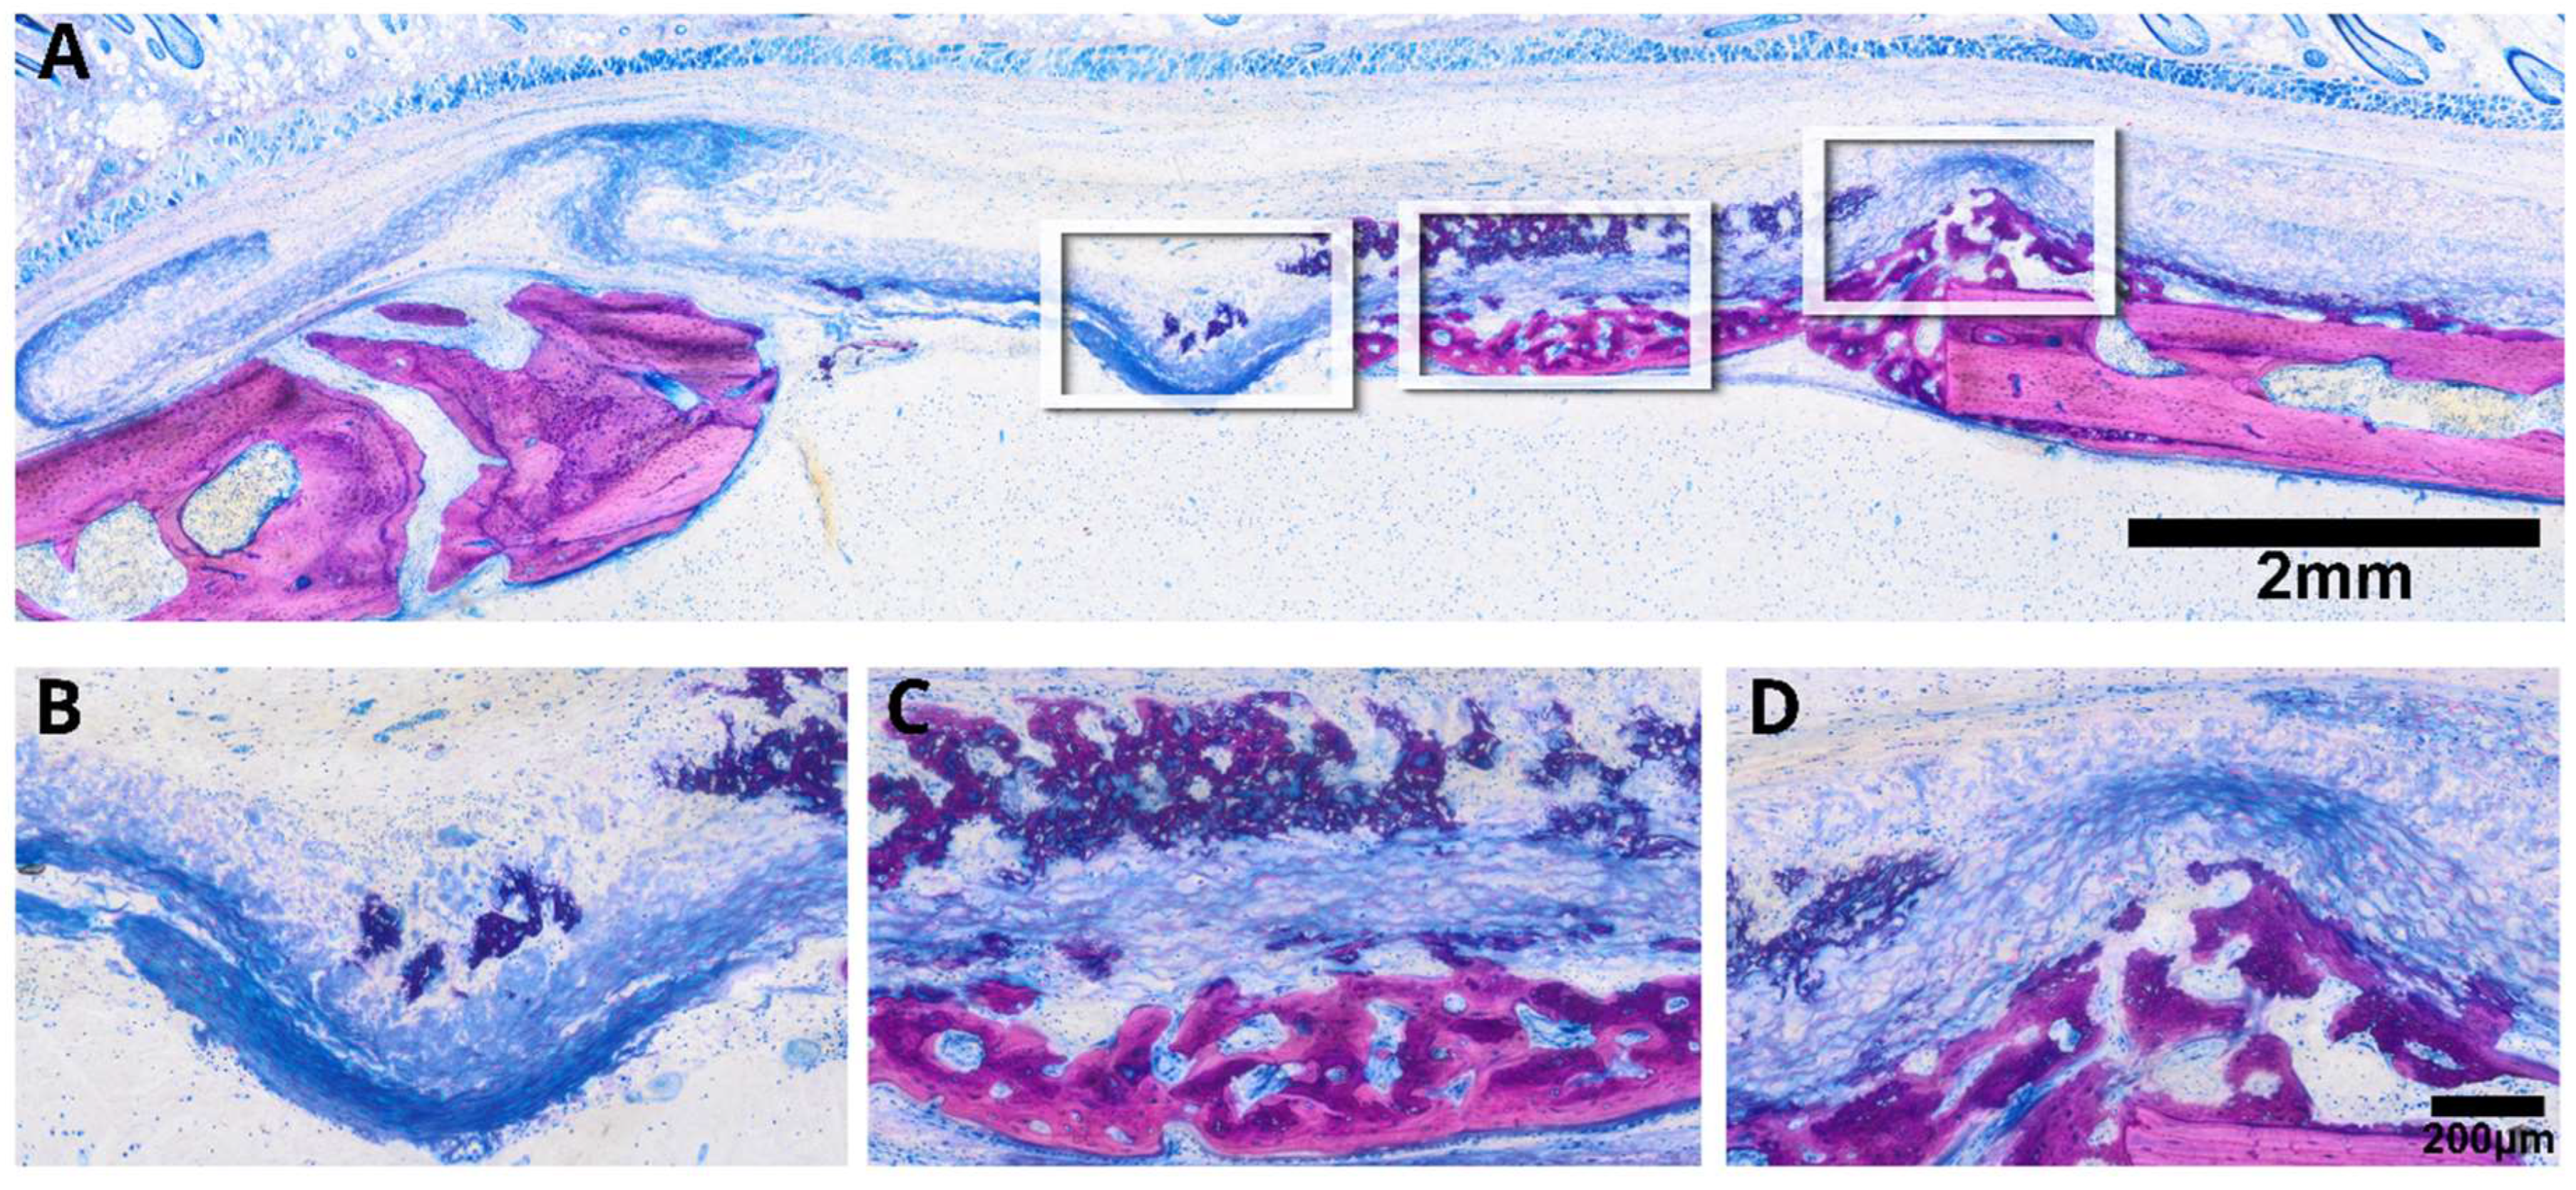

3.2. Intact Collagen Membranes: Histological Analysis